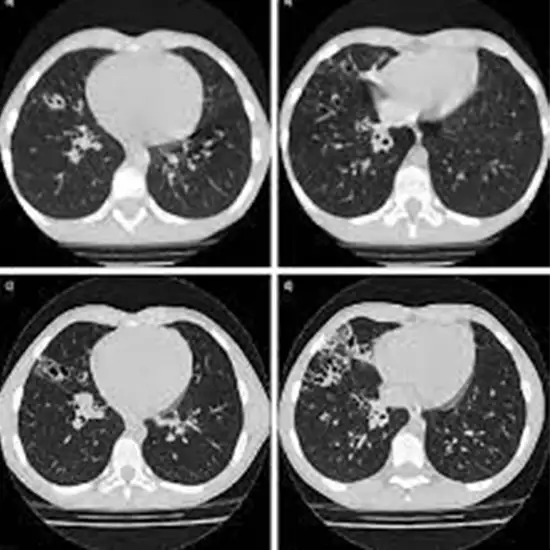

Plain HRCT (High-Resolution Computed Tomography) refers to a CT scan that produces a more precise cross-section image of the lungs than a standard chest CT. An HRCT scan of the chest is an imaging procedure that uses narrow X-ray beams to produce a high-resolution image of the lung anatomy. This test is used to evaluate lung function, detect abnormal growth in the lungs, and detect obstructions to airflows through the lungs.

HRCT Chest is an excellent imaging modality for detecting and characterising any pulmonary focus of infection or non-infectious conditions in febrile neutropenic patients. An exact etiological diagnosis is frequently possible when a specific pattern is recognised with high sensitivity and specificity.

An HRCT Thorax or HRCT Chest can aid in the diagnosis of lung issues such as tumours, pleural effusion, pneumonia, emphysema, bronchitis, tuberculosis, pulmonary embolism, COVID infection, and so on.